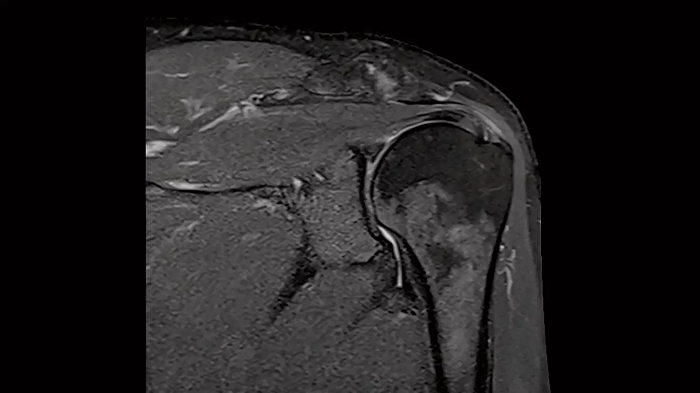

Shoulder - PD TSE FatSat

Exceptional fat suppression for the clear imaging of the shoulder.

Image Courtesy: University Hospital Erlangen, Germany | Image-ID: 4aaaa0384